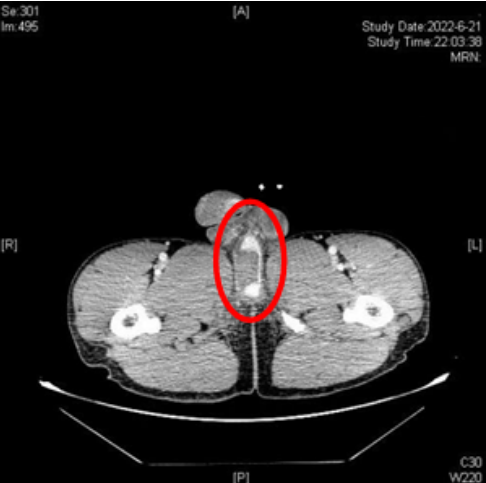

CT示患者阴茎海绵体部分撕裂,尿道海绵体断裂、造影剂外漏,海绵体周围软组织挫伤